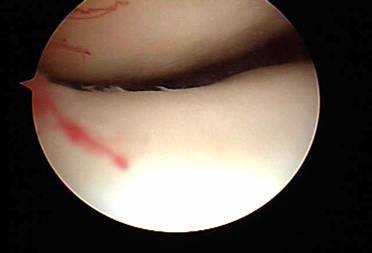

When exercises fail to improve the knee then surgery may be indicated if the symptoms are significant enough to alter activities. The most common arthroscopic surgical procedures to treat chondromalacia include chondroplasty and microfracture / abrasion procedure. A chondroplasty involves smoothing out roughened surface cartilage which can decrease friction forces on the surface cartilage and decrease symptoms of chondromalacia. An abrasion or microfracture is most useful when there is a small contained area of exposed bone or complete loss of surface cartilage. During this procedure the bone is tapped with a pick-type tool which causes bleeding in the area of exposed bone. This blood from deep inside the bone carries stem cells which can cause the bone to grow a scar type cartilage. This scar cartilage has been shown to be very effective in reducing knee pain in several orthopedic studies.